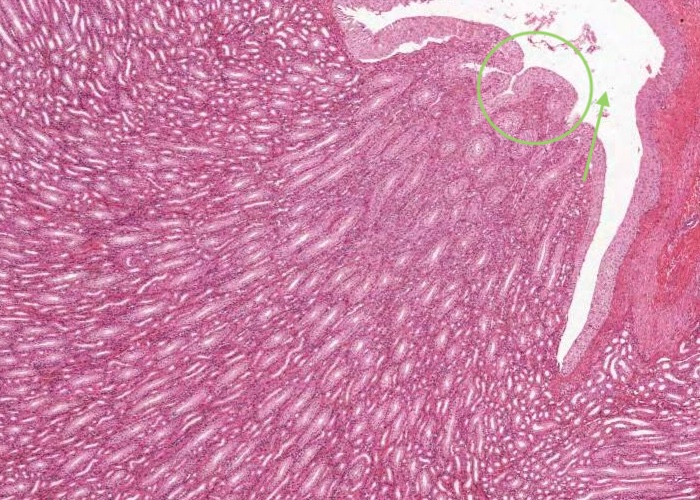

At low magnification, observe the three layers of the ureter: mucosa, muscularis and adventitia. This organization is maintained throughout the urinary passages. The mucosa of the ureter is thrown into characteristic longitudinal folds. It is made of transitional epithelium underlain by a layer of fairly cellular connective tissue (lamina propria). Quite a few lymphocytes are found in this lamina propria. The muscularis layer consists of two somewhat diffuse sheets of smooth muscle: the inner is longitudinal, and the outer is circular. Towards the bladder end it picks up a third oblique layer. This muscle produces peristaltic waves that push the urine to the bladder even when you are lying down. The adventitia is made of connective tissue and contains the nerves and blood vessels that supply the organ. One thing to note is that the ureter runs through loose connective tissue from the kidney to the bladder.

The ureter and also the other passages within the kidney through which urine flows i.e. the calyces and renal pelvis, are lined by transitional epithelium (often referred to as urothelium). The details of the layers of cells within this type of epithelium is best described in the later item "lumenal epithelium" of the bladder but generally it is 2-3 cell layers thick in the minor calyces but much thicker as you see here in the ureter and then the bladder.

Connective tissue and smooth muscle make up the remainder of the wall of the ureter. The smooth muscle is in longitudinal and circular layers so when you examine the section see if you can pick out these longitudinal and circular layers of muscle.